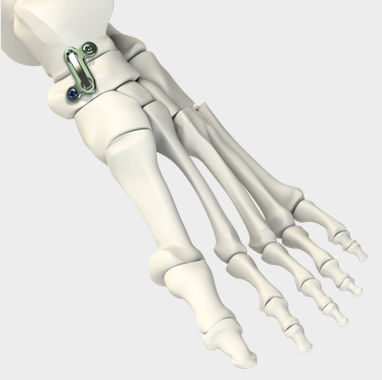

Артродез кисти

Артродез кисти 114 фотографий